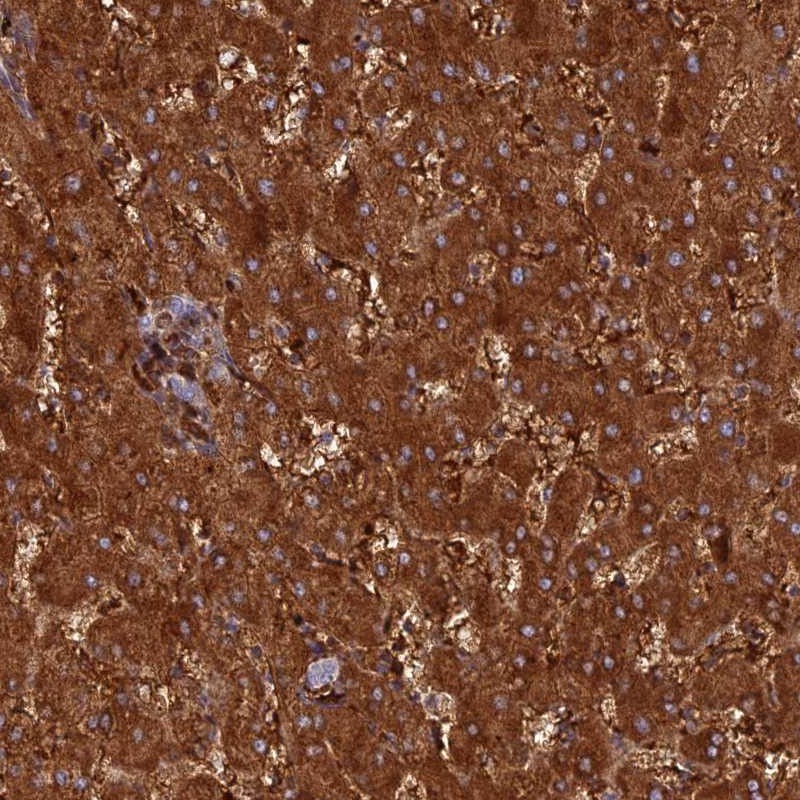

Immunohistochemical staining of human liver shows strong cytoplasmic positivity in hepatocytes.